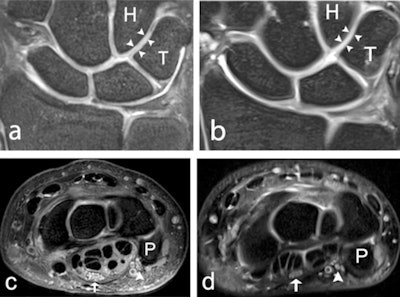

Because improved visualization using noninvasive methods could be of clinical value, a team from Lund University aimed to evaluate visualization of structures at 7-tesla compared with 3-tesla MRI using a dedicated, commercially available wrist coil.

The researchers recruited 18 healthy volunteers (three males and three females from each age decade between 20 and 49 years) and examined them with 7-tesla and 3-tesla MRI. Four musculoskeletal radiologists with 28, 18, five, and 1.5 years of experience underwent a training session before image interpretation to ensure scoring conformity and then graded 2D and 3D images on a five-level visual grading characteristics (VGC) scale for visibility of ligaments, cartilage, nerves, trabecular bone, and tendons, as well as for overall image quality (i.e., edge sharpness, perceived tissue contrast, and presence of artifacts). Scores of 1 indicated "unacceptable," while scores of 4 indicated "good" and scores of 5 indicated "excellent" image quality.

Robust results

The team graded all evaluated anatomical structures, including ligaments, trabecular bone, cartilage, nerves, and tendons, as better visualized at 7 tesla compared with 3 tesla, with an area under the curve (AUCVGC) of 0.62-0.88 (95% confidence interval [CI] 0.50-0.97, p = < 0.0001-0.03) using either 2D or 3D imaging. Specifically, 7 tesla was significantly superior to 3 tesla in the evaluation of edge sharpness and perceived tissue contrast. There was no significant difference in grading regarding artifacts. Importantly the results also revealed that MRI of the wrist at 7 tesla with a commercially available wrist coil is feasible at similar acquisition times as for 3 tesla MRI.

Limitations of the current study were the small number of subjects and the lack of pathology in the study population. Also, the 3D sequences were optimized for ligament visualization, which may have resulted in a less optimal visualization of other structures. However, the authors underlined that the study demonstrated overall, that wrist structures are better visualized at 7 tesla compared with 3 tesla, this better visibility and delineation likely to translate into better detection and definition of pathology.